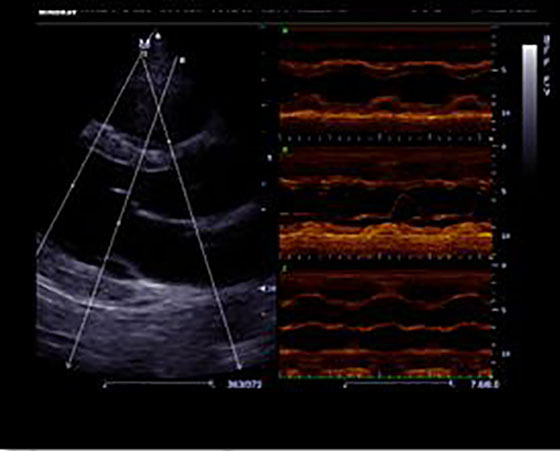

Free Xros M™

Позволяет получить точные анатомические измерения посредством свободного размещения линий М-режима под любым углом. Оптимальное качество изображения достигается с помощью одновременного использования до 3 линий М-режима.